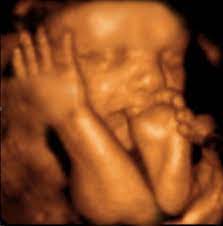

Sweet Baby Face 3d 4d Ultrasound

Sweet Baby Face 3d 4d Ultrasound. Book an appointment in Louisville or Elizabeth today. We Specialize in 4DHD Ultrasound 3D Ultrasound Photography and Baby Boutique items.

Sweet Baby Faces Ultrasound Studio. The entire scanning session video will be provided via email for unlimited sharing with friends and family. 1479 likes 26 talking about this 691 were here. Now you can see your baby up close and personal with a 3D4D HD ultrasound from Sweet Baby Face.